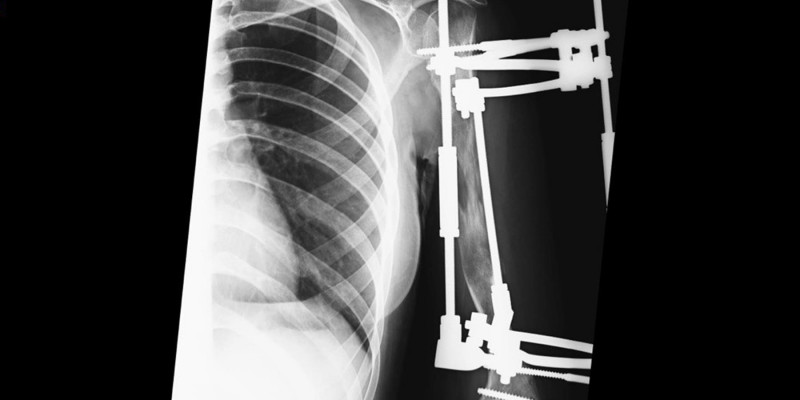

«В сентябре 2024 года мы провели операцию, – рассказал врач-травматолог-ортопед детского травматолого-ортопедического отделения Клиник СамГМУ Никита Лихолатов. - Удлинение верхней конечности на такую большую величину за одну операцию – смелое решение, мы понимали, что есть риски осложнений. Но девочка была настроена оптимистично и нам хотелось помочь. Проконсультировавшись с коллегами из других медучреждений, мы разработали тактику ведения пациента. Для удлинения на такую большую величину подходит метод Илизарова, при котором поэтапно выращивается своя собственная кость. Но ситуация осложнялась тем, что у девочки была угловая деформация плеча, поэтому нам нужно было единомоментно еще скорректировать эту деформацию. Первую часть мы выполнили в операционной, в процессе также установили аппарат внешней фиксации, а через двое суток после операции необходимо было скорректировать второй компонент. Это делается под местным обезболиванием, но все равно неприятно. Девочка на удивление стойко перенесла процедуру».

Как пояснил врач, обычно растяжение у детей в аппарате Илизарова проводится на 1 мм в сутки – костные фрагменты раздвигаются, между ними образуется мягкая костная мозоль, которая в дальнейшем перестраивается в кость. Но так как девочке было уже 17 лет, темп коррекции должен был быть ниже, чтобы не разорвать мягкий компонент. Поэтому с аппаратом она находилась достаточно длительное время, в течение которого могла ходить на учебу, заниматься всеми бытовыми делами и не была ограничена физически. Недавно аппарат сняли, теперь пациентка разрабатывает локтевой и плечевой суставы и продолжает наблюдаться у врачей. Специалистам удалось устранить косметический дефект и дать девушке возможность полноценно выполнять работу рукой.